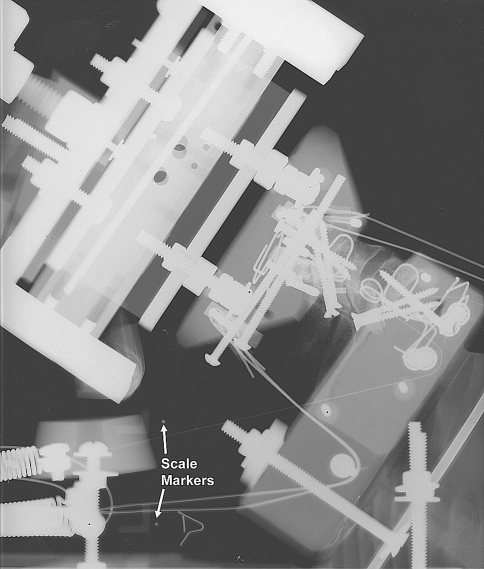

Fig. 2.

Lateral radiograph of the functional spinal unit (specimen #8; C5/6) mounted atop an extension wedge on the sled, with radio-opaque scale markers

Four fresh-frozen human osteoligamentous cervical spine specimens (C3 to T1) were carefully dissected of all non-osteoligamentous soft tissues. The average age of the specimens was 62 years (range 57–79 years) and there were two male and two female donors (Table 1). Other than normal age-related degenerative changes, the specimens had no history of cervical spine injury or disease that could have affected the osteoligamentous structures. The specimens were dissected into C3/4, C5/6, and C7/T1 functional spinal units (FSUs) resulting in four FSUs at each spinal level. Each FSU was mounted in resin at the upper and lower vertebrae such that the superior endplate of the lower vertebra was tilted anteriorly by 12.5° (SD 6.2°). The vertebrae were rigidly secured within the mounts using screws and wiring [19], as shown in the lateral radiograph (Fig. 2). Motion tracking flags, each with three non-collinear markers, were rigidly fixed to both mounts. The lower mount was rigidly fixed to a 55° extension wedge on a custom built sled apparatus (Fig. 3). A mass of 3.3 kg with sagittal, horizontal, and frontal plane moments of inertia of 0.019, 0.014, 0.015 kg m2, respectively, was rigidly attached to the upper mount. The average (SD) coordinates of its center of mass in the neutral posture, expressed in the endplate coordinate system of the lower vertebra, were −12.4 (19.7) mm for Z, 153.9 (7.1) mm for Y, and 0.0 (0.0) for X. The FSU and mass were stabilized using simulated compressive muscle forces, applied via bilateral cables originating from the upper mount at the four locations indicated in Fig. 3. Each cable was anchored to a separate preloaded spring, with a stiffness of 4.0 N/mm. Cables 1 and 3 were connected directly to the springs, while cables 2 and 4 ran through pulleys within the lower mount. The preloads were 15 N in cables 1 and 4 and 30 N in cables 2 and 3, resulting in an intervertebral compressive preload of 180 N. This preload is in good agreement with the estimated in vivo C4/5 compression of 122 N in the relaxed posture [18]. This constituted the BFD model. It was developed through extensive preliminary trials and was found to consistently produce BFD.